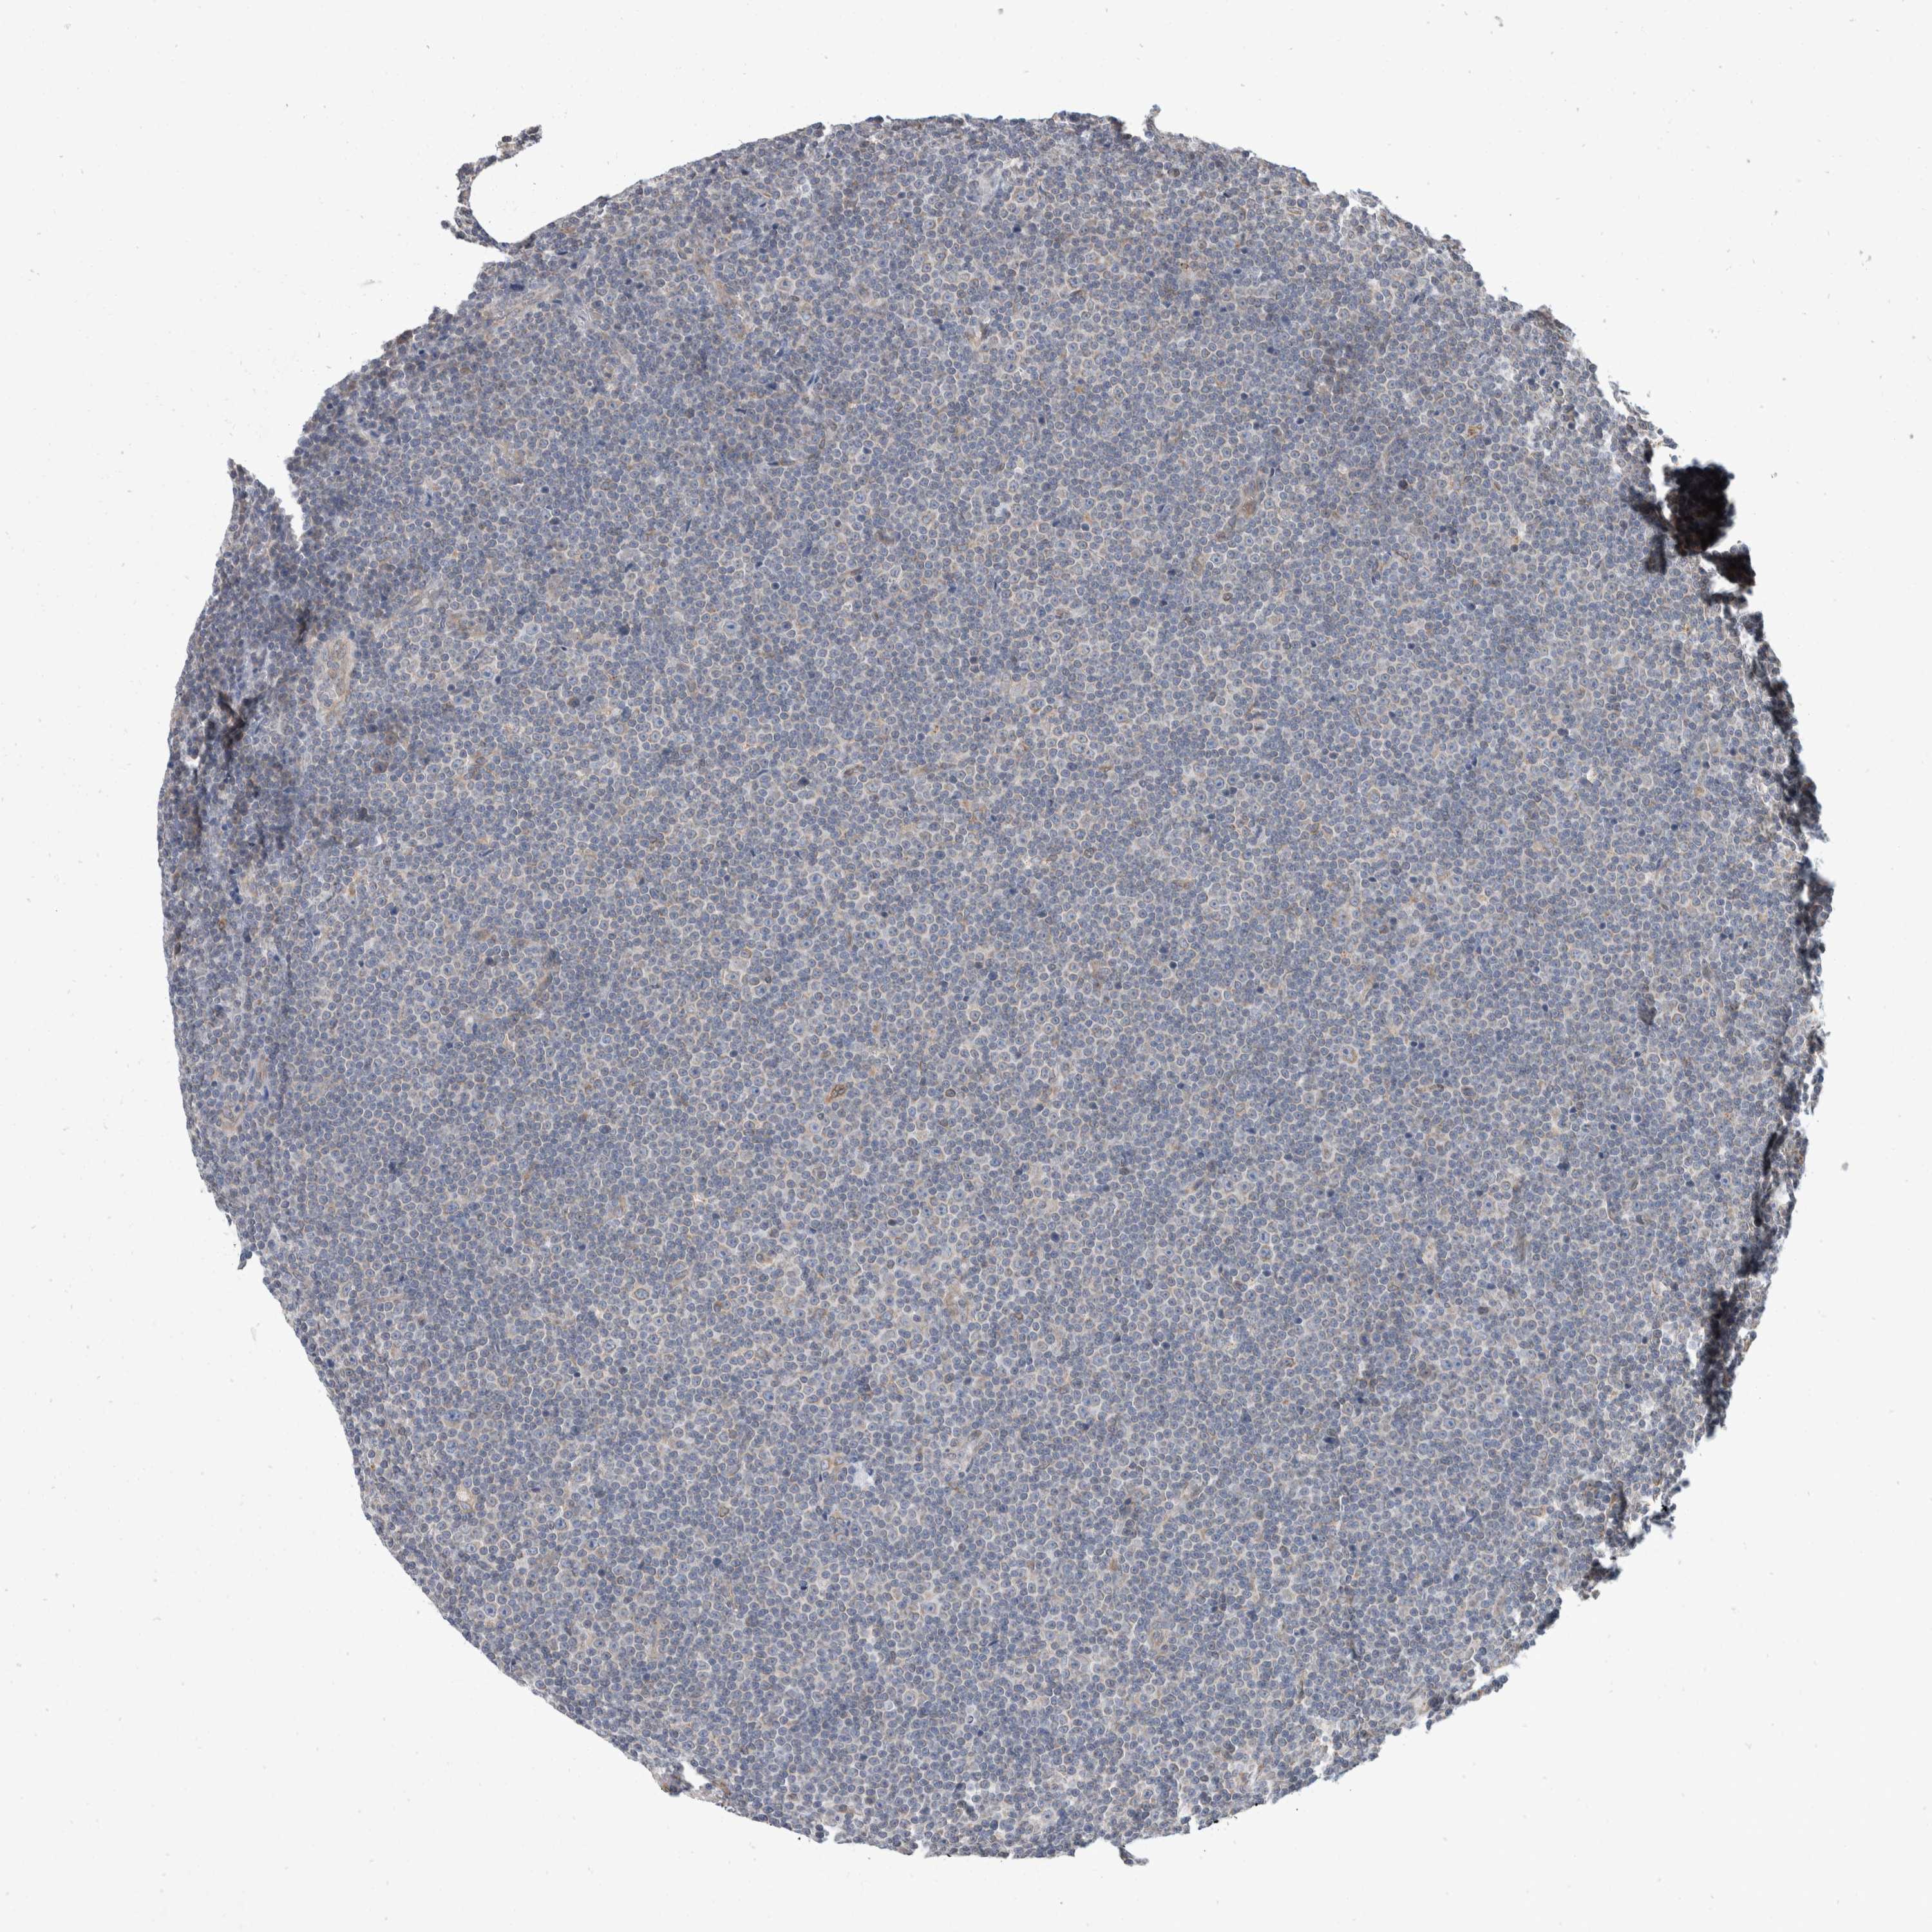

CANCER LYMPHOMA Show tissue menu

LYMPHOMA - Protein expressioni

A mouse-over function shows sample information and annotation data. Click on an image to view it in a full screen mode. Samples can be filtered based on level of antibody staining by selecting one or several of the following categories: high, medium, low and not detected. The assay and annotation is described here.

Each image is clickable and will lead to virtual microscopy that enables deeper exploration of all samples and also displays staining intensity scores, fraction scores and subcellular localization as well as patient and tissue information for each sample.

Antibody HPA023892

Staining

High

Medium

Low

Not detected

Intensity

Strong

Moderate

Weak

Negative

Quantity

>75%

75%-25%

<25%

None

Location

Nuclear

Cytoplasmic/membranous

Cytoplasmic/membranous,nuclear

Hodgkin's disease, NOS

Malignant lymphoma, non-Hodgkin's type, High grade

Malignant lymphoma, non-Hodgkin's type, Low grade